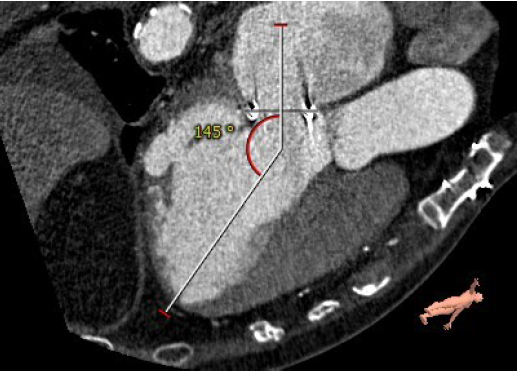

主动脉与生物瓣轴夹角76°

左室与生物瓣轴夹角145°